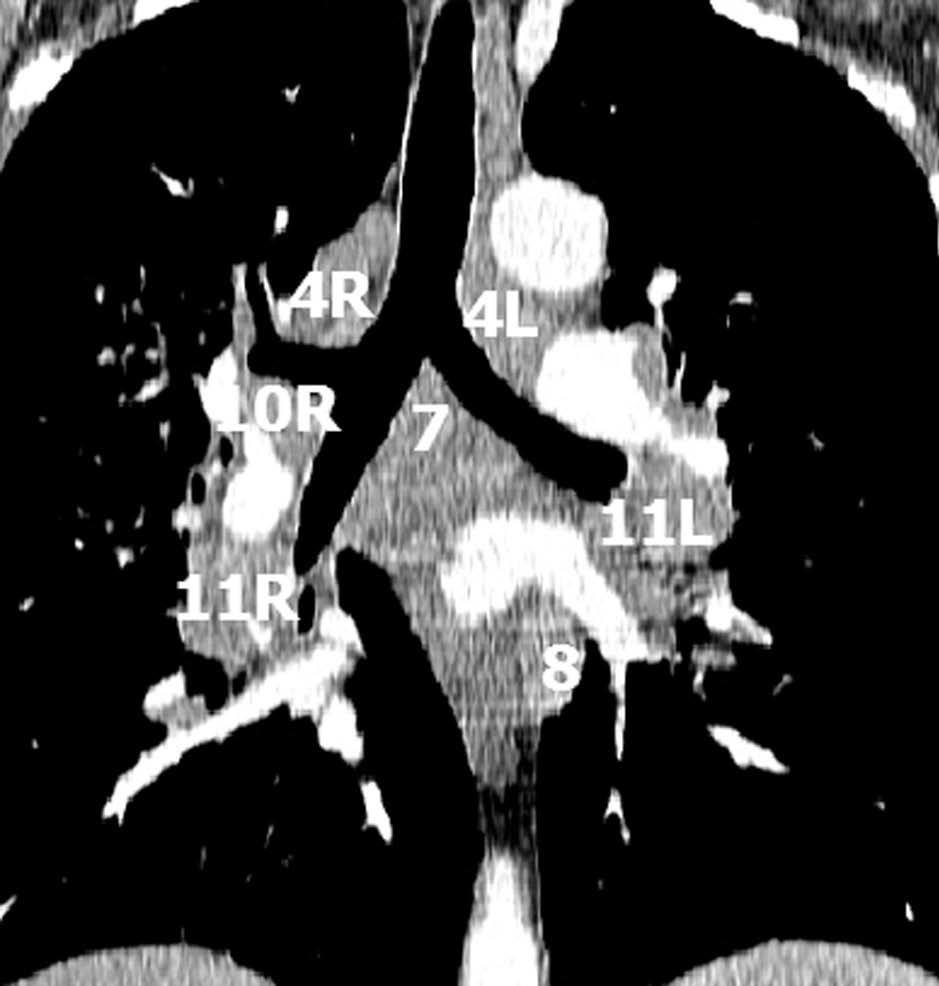

La precisión de la TC para predecir la afectación ganglionar mediastínica, pese a la ayuda que suponen las reconstrucciones MPR y 3D en la valoración de determinados territorios ganglionares (espacio subcarinal, hilio o ventana aortopulmonar) (fig. 11), sigue teniendo muchas limitaciones. El único criterio que se emplea para considerar que un ganglio es patológico es el tamaño (cuando el eje corto es mayor de 10 mm, salvo en el espacio subcarinal que se acepta hasta 12 mm). El empleo únicamente de criterios de tamaño hace que la TC sea una técnica poco precisa en la valoración de la afectación ganglionar. En un metaanálisis reciente13 la sensibilidad global de la TC para estadificar el mediastino fue de un 57%, con una especificidad del 82%, un valor predictivo positivo (VPP) del 56% y un valor predictivo negativo (VPN) del 83%. Lo que es innegable es la capacidad de la TC para mostrar un mapa de los ganglios tanto hiliares como mediastínicos (fig. 12), lo cual es de gran utilidad en la determinación del factor N. La valoración del territorio hiliar puede ser compleja por la agrupación de estructuras vasculares, por lo que además de la opacificación adecuada de éstas, es de utilidad la identificación de la pérdida del ángulo de la bifurcación (carina secundaria), ya que el eje corto significativo en este territorio es de 3 mm. Como ya hemos comentado, también es de gran ayuda en esta localización el empleo de reconstrucciones (fig. 11)5.

Fig. 12.--Estaciones ganglionares para la estadificación del cáncer de pulmón. Las reconstrucciones multiplanares (MPR) son de gran ayuda para precisar los territorios ganglionares afectos. Correlación de los territorios ganglionares entre el mapa ganglionar de Mountain y Dressler y una reconstrucción coronal de un paciente con afectación adenopática mediastínica e hiliar bilateral. (A y B) Ganglios mediastínicos superiores e inferiores e hiliares. (C y D) Ganglios aórticos. AP: arteria pulmonar. Ao: aorta.